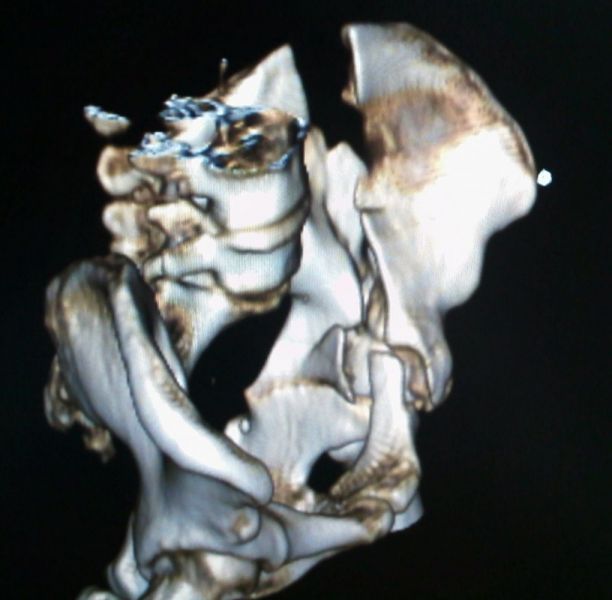

4. Posterior dislocation of the right hip with posterior acetabulum fracture in a 40-year-old male.

Treatment: 1st stage; closed reduction of the dislocation 2nd stage; open reduction of the acetabulum fracture with internal fixation

Ι. Obturator view of the right acetabulum shows the dislocation of the right hip II. Obturator x-ray right acetabulum shows the reduction of the hip, the red arrow shows the fracture III. Iliac x-ray acetabulum after the procedure shows the implant work (the patient referred to Mr. Antonios Papasotiriou who fixed the acetabulum)